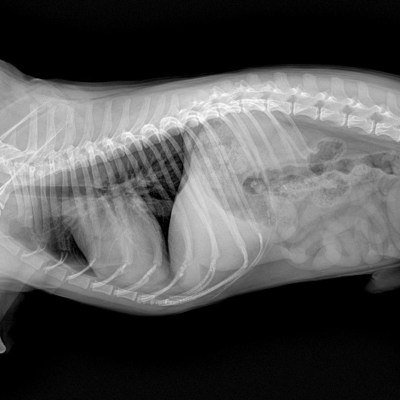

Röntgen ve Laboratuvar Testleri

Hayvanınızın iç organları ve kemik yapılarının sağlığını incelemek için röntgen ve diğer görüntüleme yöntemlerini kullanıyoruz. Kan testleri, idrar testleri gibi laboratuvar analizleri yapılır.